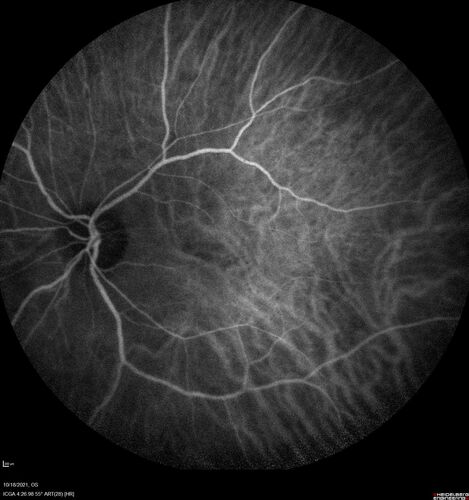

Severe Syphilitic Placoid Chorioretinitis

68 year old man 3 months ago the vision started fading in both eyes.  Just sitting here he can see some light out of his right eye. The patient denies any recent illness or travel.

VA: OD: LP, OS: 4/200

IOP: 9, 13

Anterior segment: 1+ cell/ 2+ flare OU and 2+ NS and anterior vitreous cells

Labs Reactive RPR 1:256, FTA-ABS - reactive - Patient was admitted to hospital for IV PCN and recovered vision almost completely in the left eye and some in the right eye.